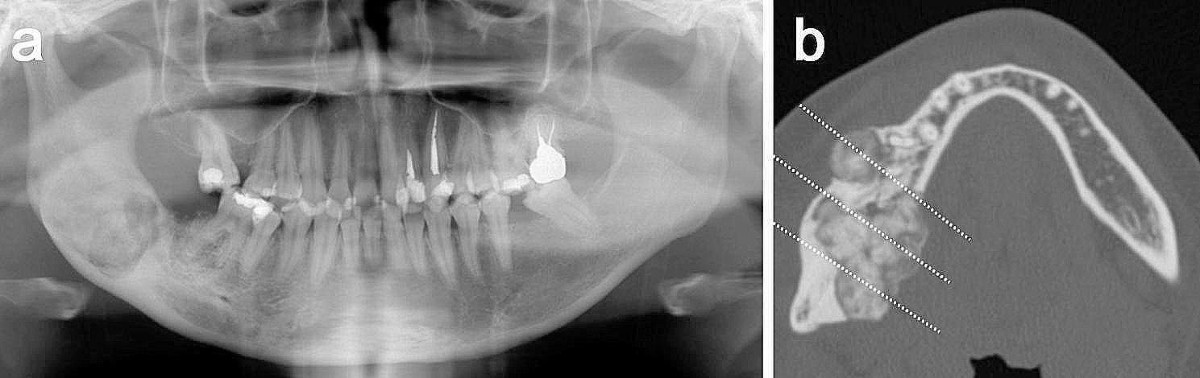

Cementoblastoma

Cementoblastoma - Wikipedia Apical Radiopacities - Radiodontics Cementoblastoma: Features, Diagnosis, and Treatment Cementoblastoma. Classic appearance of a sclerotic tumor fused ... ❇ Benign Cementoblastoma Radiology: ▶ Location: → 78% in ... Cementoblastoma